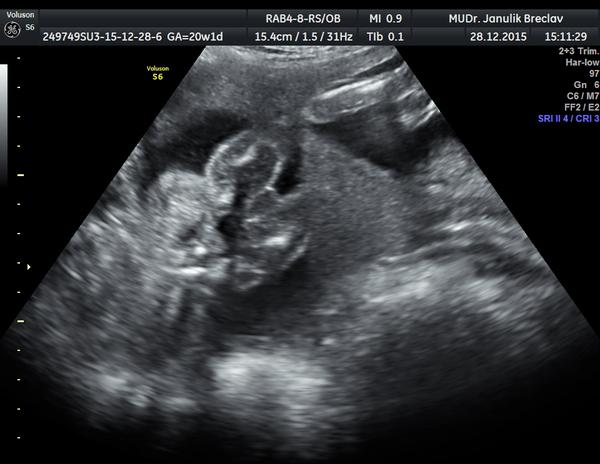

tak moje MUDr. na 2D utz taky vidí holčičku, ale prej když je tatínek ze 4 bratrů tak to pro jistotu ještě příště zkontroluje... 😀 Holky máte tady někdo muže z rodiny kde jsou samí chlapi a narodila se vám holka??

U nás to nakonec bude asi opravdu ten klucik, no podle mého dnešního utz ve 32t, snad jsem viděla dobře. Ptát se mi nechtělo ať tam je i tak nějaká ta nejistota 😉 .

@monikaaaa24 Ahoj, novou fotku nemám, dr. říkala, že jak už je mimčo velký, tak je to vidět čím dál hůř.

@satynka no nebyl si jistej a nechtelo se mu do toho a kdyz jsem rekla ze kvuli tomu jsem k nemu sla na 3D, tak rekl že to jde na 3D poznat hur nez na 2D ale ze to vypada asi na princeznu..